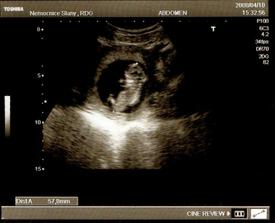

Majdulka (oficiálně Markéta) se narodila 21. 10. 2008 v 19:52 a měřila 50 cm a vážila 3530 g.